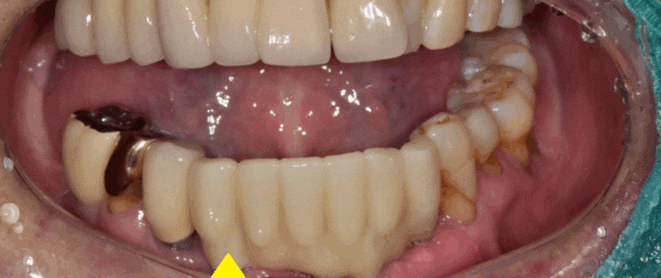

70대 남성 환자분이 오셨습니다.

이미 다른 치과에서 진료 중인데

진단을 다시 받고 싶다 하셨습니다.

x-ray 촬영 말고

그냥 육안으로만 보고 말씀해 달라고 하셨는데요.

이럴 때 의료진으로써 참 난감한 순간이긴 합니다.

눈으로 보는 것은 뿌리 쪽과

잇몸 뼈 상태를 확인할 수 없기 때문입니다.

육안 검사 후 필요시 x-ray를 찍기로 하고

환자분을 만나 뵙게 되었습니다.

환자분의 요청대로 육안 검사를 시행

보철이 한지 오래되어 뿌리가 노출되고

손으로만 건드려도 흔들거리는 상황

"환자분 x-ray를 찍어보지 않았지만

치아 흔들림이 너무 많아요.

이건 잇몸뼈가 많이 녹아서 그런건데

뽑고 임플란트가 필요합니다"